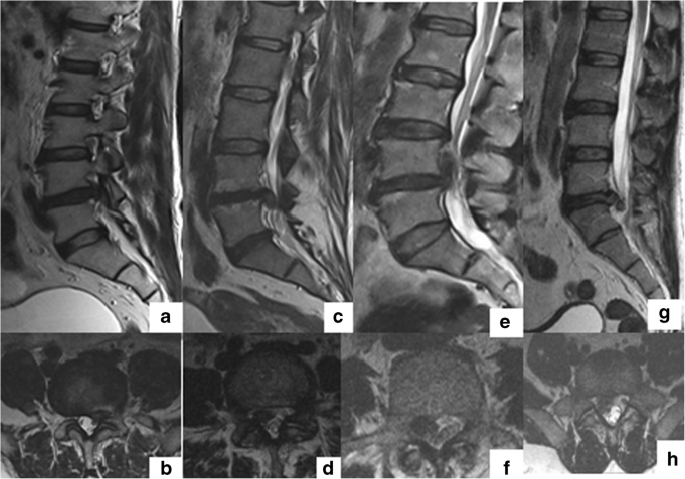

Factors That Influence Neurological Deficit And Recovery In Lumbar Disc Prolapse A Narrative Review Springerlink Breast cancer experts locations & directions research & clinical trials resources.